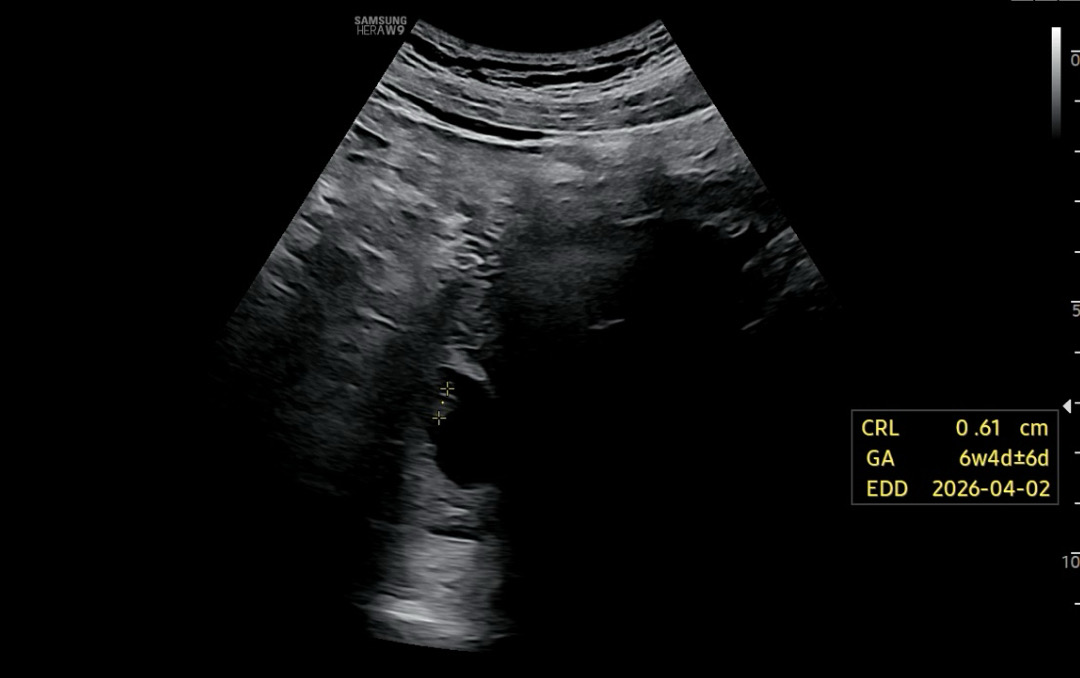

6주 4일차 심장소리 듣고 왔어요 !

10주까지는 질촘파 하는 줄 알았는데 이번에 배촘파로 진행했어요 3분 동안 했는데 선생님 눈과는 달리 제 눈에는 심장 반짝임도 잘 안보이고 소리도 잘 안들렸는데 후굴자궁이라서 그렇다네요 🤣 저에 대해 새로이 많이 알아갑니다 2주 후에 젤리곰이 보고싶은데... 여전히 잘 안보일거 같아서 걱정이에요 ㅠㅠㅠ 선생님께 제가 질촘파 해달라고 요청해도 되는 부분일까요 ?